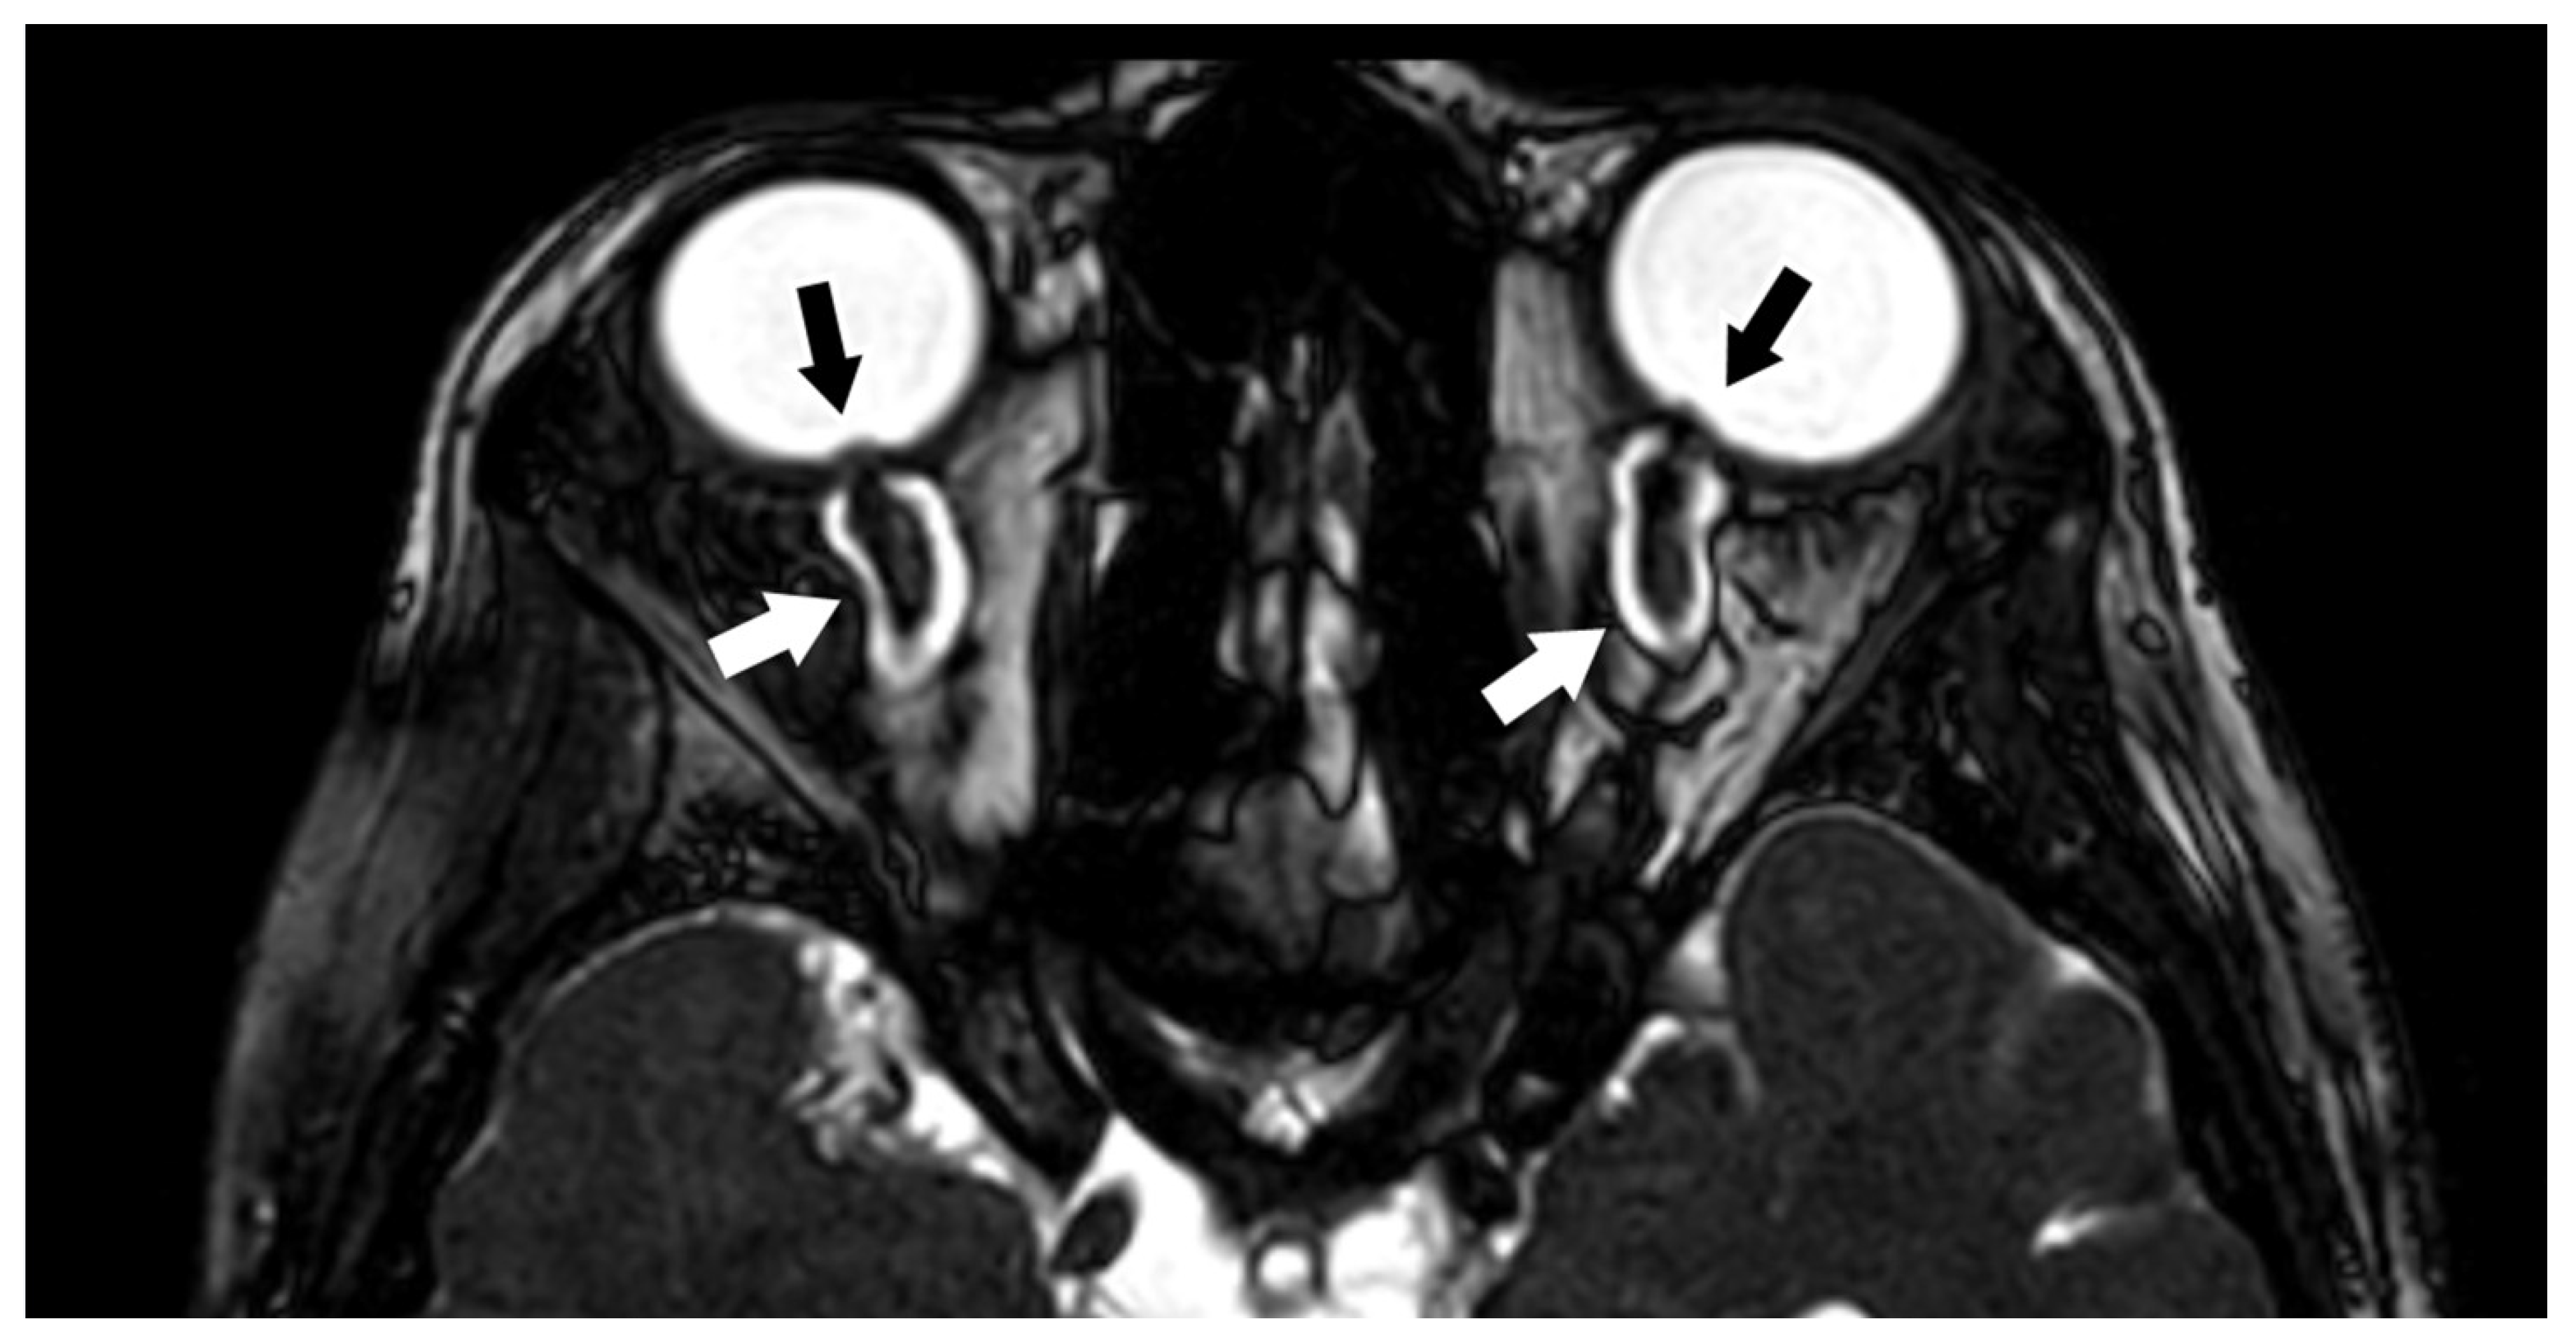

3.1.2. Optic Nerve (II) and Orbital Masses

- Nagarajan, K.; Venkataraman, A. Thin-section 3D Steady-State MRI in Optic Nerve Coloboma. Neuro-Ophthalmology 2021, 45, 281–282. [Google Scholar] [CrossRef] [PubMed]

- Seitz, J.; Held, P.; Strotzer, M.; Müller, M.; Völk, M.; Lenhart, M.; Djavidani, B.; Feuerbach, S. Magnetic resonance imaging in patients diagnosed with papilledema: A comparison of 6 different high-resolution T1- and T2(*)-weighted 3-dimensional and 2-dimensional sequences. J. Neuroimaging 2002, 12, 164–171. [Google Scholar] [CrossRef]